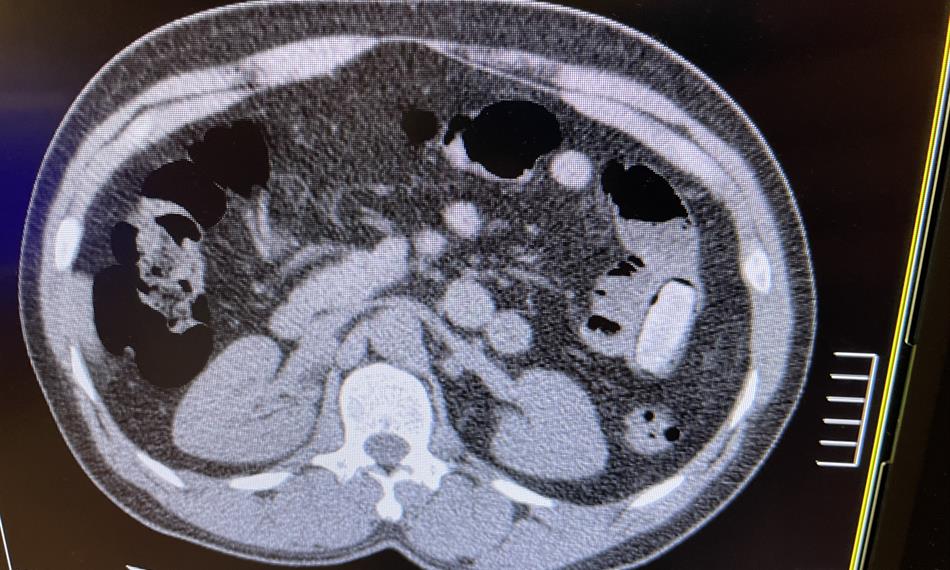

Pětačtyřicetiletý cizinec cestoval linkovým autobusem na trase Brusel – Praha, přičemž cílovou destinací mělo být Rakousko.  Při celní kontrole na něj pozitivně reagoval služební pes vycvičený na vyhledávání drog, označil ho a muž byl pro podezření přepraven do zdravotnického zařízení. Následné rentgenové vyšetření prokázalo výskyt cizích předmětů v tělních dutinách cestujícího a laboratorní rozbory potvrdily podezření celníků, že se jedná o kokain. Během jednoho dne vyloučil organismus muže postupně všechny kontejnery s drogami.